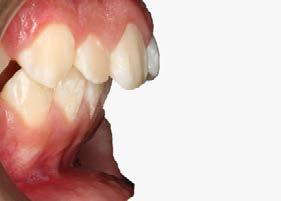

Manejo interceptivo de maloclusión clase II esqueletal

Manejo interceptivo de maloclusión clase II esqueletal con remanente de crecimiento: reporte de un caso clínico

Introducción: La maloclusión clase II provoca proporciones irregulares en el perfil facial. Puede deberse a un maxilar adelantado y a incisivos superiores proinclinados y protruidos. Esta condición puede corregirse mediante el uso de aparatos ortopédicos en pacientes en crecimiento.

Objetivos: Conseguir clase I canina, controlar el crecimiento vertical, disminuir la convexidad esqueletal, reducir la sobremordida horizontal y mejorar el perfil facial. Caso clínico: Paciente femenina de 9 años, clase II esqueletal, biotipo dolicofacial, perfil convexo, clase II molar, clase II canina y proinclinación de incisivos superiores e inferiores. Resultados: Se logró clase I canina, se controló el crecimiento vertical, se redujo la convexidad esqueletal, se mejoró la sobremordida horizontal y el perfil facial. Conclusiones: El uso combinado de aparatos ortopédicos y aparatología fija en pacientes en crecimiento, junto con un diagnóstico y plan de tratamiento acertado, permite obtener resultados exitosos y estables en la corrección de estas maloclusiones.

Palabras clave: arco extraoral, clase II, ortopedia, cantilever, crecimiento.